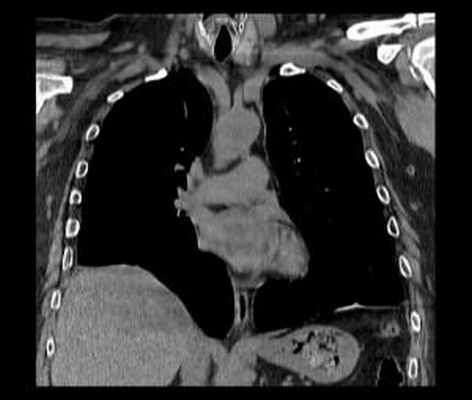

КТ. Наиболее информативным методом исследования является компьютерная томография, дающая полную информацию о степени релаксации и характере изменений органов грудной и брюшной полостей. Во всех случаях релаксации, даже при небольшой ее выраженности, наблюдается ателектаз и воспалительные изменения базальных сегментов легкого. С внедрением компьютерной томографии практически отпала надобность в остальных традиционных методах дифференциальной диагностики.

Релаксация правого купола диафрагмы на КТ